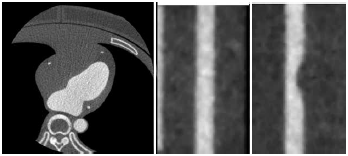

a 心臓周辺の拡大再構成

b 正常な模擬冠動脈のMPR

c 狭窄のある模擬冠動脈のMPR

図4に、前述の冠動脈CTAのための胸部ファントムのCT画像を示す。図4aの水平断の画像では、椎体や左室内腔の造影剤に由来するストリークアーチファクトやビームハードニングアーチファクトが発生しており、実際の臨床で得られるものに近い画質の画像が得られた。図4b・図4cに示す模擬冠動脈のmulti-planar reconstruction:MPRを観察することで模擬病変の視認性の評価が可能であり、線量決定のための参考画像として有用であった。また、冠動脈モジュールを対象としてTTFを計測することで、実際の臨床に近い環境の分解能特性を計測することができた。